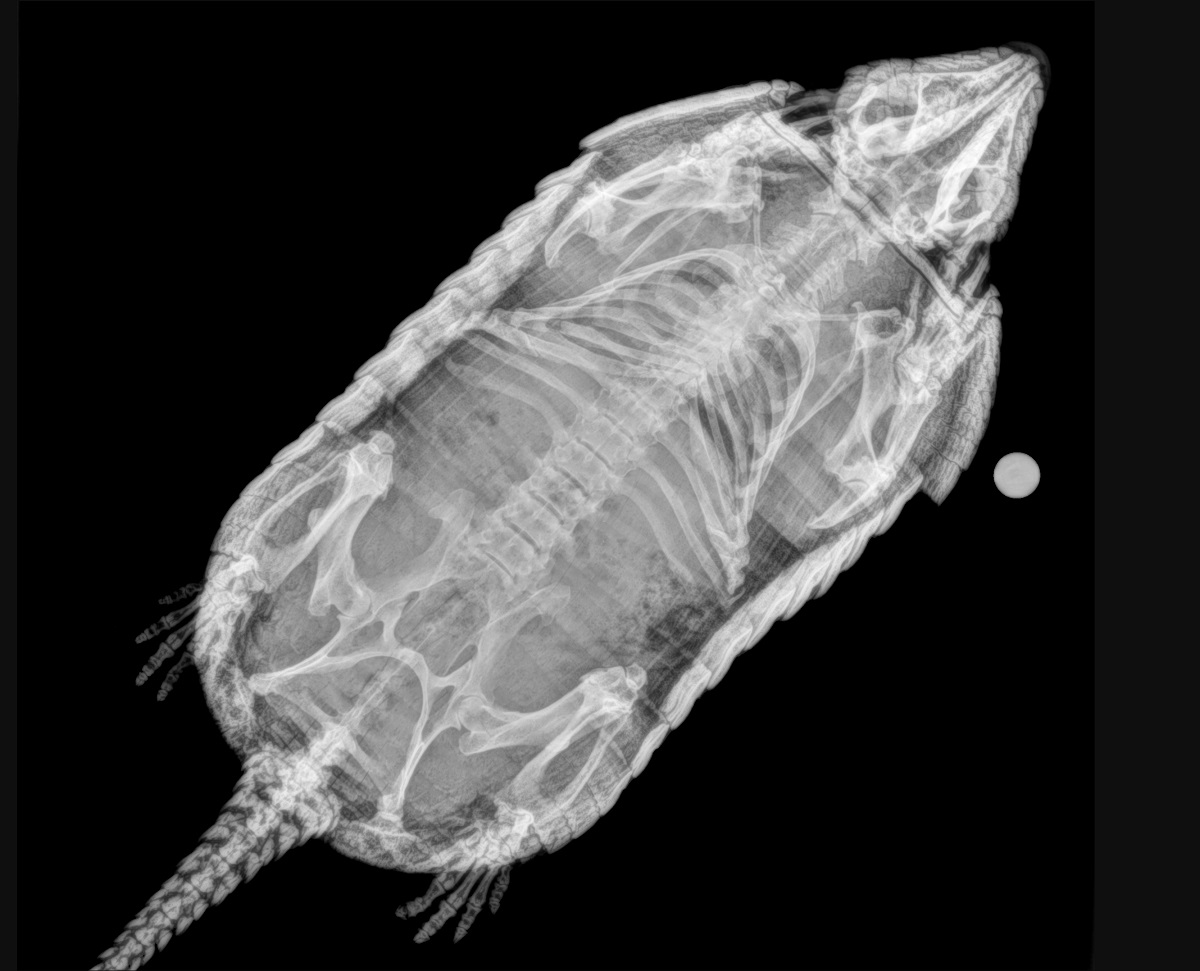

Este procedimiento diagnóstico permite a nuestros expertos brindar una excelente atención médica. Al exponerlos a los rayos X, el equipo puede tomar fotografías de las partes óseas internas de los animales, comprobando la existencia de lesiones o enfermedades que a simple vista no podrían ser identificadas.

Pero, ¿cómo se toma una radiografía de un tigre de Sumatra, de un cálao Gorginegro, un flamenco o un encantador armadillo de tres bandas?

Sin embargo, otros animales no necesitan de esta inmovilización química para hacerles radiografías, es el caso de los armadillos. Con ellos basta con un manejo físico y una buena parte de colaboración voluntaria por su parte. “En ocasiones nos valemos de un proceso de entrenamiento previo que llamamos ‘entrenamiento médico’, en el que el animal recibe una recompensa si nos permite realizar estos estudios de manera voluntaria, sin sujeción física y sin anestesia”.